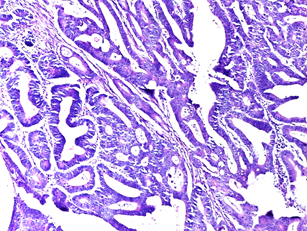

This histology image (Figure 4.1) demonstrates that

moderately differentiated adenocarcinomas were predominantly observed in the

left colon within the study population.

Figure 4.1. Moderately

differentiated adenocarcinoma – left colon (H&E).